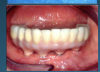

Many factors should be considered when designing implant-supported restorations to reduce the risk of peri-implantitis affecting physical removal of bacterial plaque at the FMG. Included are oral hygiene devices, accessibility, prosthetic shapes, and patient ability to comply with oral hygiene procedures. The design should be conveniently hygienic so patients can easily comply with the recommended oral hygiene procedures. Physical removal of bacterial plaque on the intaglio surface at and above the FMG reduces the risk of peri-implantitis in the sub-gingival transmucosal tissue around dental implants. The original fixed prosthetic design presented by Branemark, a "High water design", provided access to all surfaces for oral hygiene management without a patient complaint of food accumulation (Figure 9 and Figure 10). Notably, relief above the gingiva was not patient complaint with this design. Lack of embrasure access to the FMG and intaglio surfaces for oral hygiene management can lead to peri-implantitis (Figure 11 and Figure 12). Stein recommended a convex modified ridgelap pontic design with lingual and palatal access to facilitate plaque removal from the intaglio surface under pontics in fixed prosthetics with dental floss.20 These shapes should be standard for fixed implant-supported restorations whether individual or multi-unit restorations made of ceramo-metal or milled zirconia (Figure 13 through Figure 16).

(9.) Branemark “High water” design.

Figure 9

(10.) Branemark “High water” design.

Figure 10